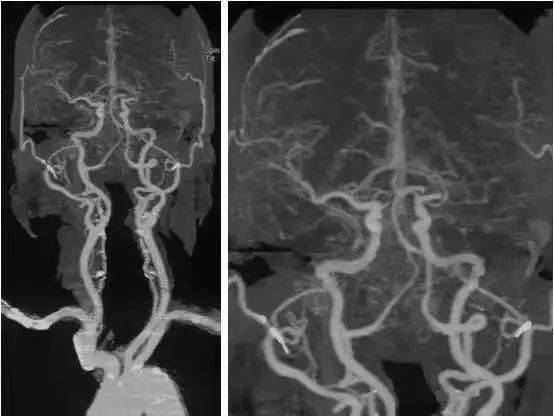

MS的 MRI特點(diǎn)。

側(cè)腦室周圍、半卵圓中心、胼胝體與腦室間可見類圓形或融合性斑塊, T1W I低信號 、T2WI高信號,大小不一,常見于側(cè)腦室前角和后角周圍,大融合性斑塊多累及側(cè)腦室體部, 腦干、小腦、脊髓可見不規(guī)則斑塊。 MS患者病程較長可伴腦室系統(tǒng)擴(kuò)張、腦溝增寬等腦白質(zhì)萎縮征象。

T2W I顯示大腦白質(zhì)MS斑塊較好, 質(zhì)子密度加權(quán)像顯示腦干和小腦斑塊較清晰,T1W I可鑒別MS陳舊與新鮮斑塊,前 者 T1W I呈明顯低信號,注 射 Gd-DTPA后不強(qiáng)化,后者呈模糊等信號,有顯著強(qiáng)化效應(yīng)。 MRI診斷顱內(nèi)多發(fā)性脫髓鞘病變注意事項(xiàng)。

MRI在臨床的廣泛應(yīng)用發(fā)現(xiàn)許多顱內(nèi)多發(fā)性病變, 腫瘤、腦梗死、寄生蟲病等??纱_診, 許多原因不明的顱內(nèi)多發(fā)性病變往往根據(jù)其形態(tài)及分布范圍被歸為“脫髓鞘”病變,導(dǎo)致對脫髓鞘及脫髓鞘疾病概念認(rèn)識的混亂。 腦室旁T2W I高信號可見于多種病理過程,甚至正常的老年人,但老年人改變常較輕微, T2W I顯示數(shù)個不對稱的界限清楚、緊鄰腦室表面病灶常提示MS, 與纖維束走行一致的放射性分布的脫髓鞘區(qū)更有診斷意義,急性期病灶有增強(qiáng)效應(yīng)。

顱內(nèi)多發(fā)性脫髓鞘病變典型地見于多發(fā)性硬化患者, CNS脫髓鞘病變是自身免疫機(jī)制導(dǎo)致。然而,多種神經(jīng)系統(tǒng)病變?nèi)缪h(huán)障礙、中毒、感染、變性及營養(yǎng)障礙等均可導(dǎo)致脫髓鞘或類似脫髓鞘病變,是廣義的脫髓鞘疾病,后者應(yīng)根據(jù)患者的臨床表現(xiàn)、自然病程、病變影像學(xué)特點(diǎn)及治療反應(yīng)等與MS鑒別,避 免 CNS脫髓鞘病變的臨床誤診或過度診斷。